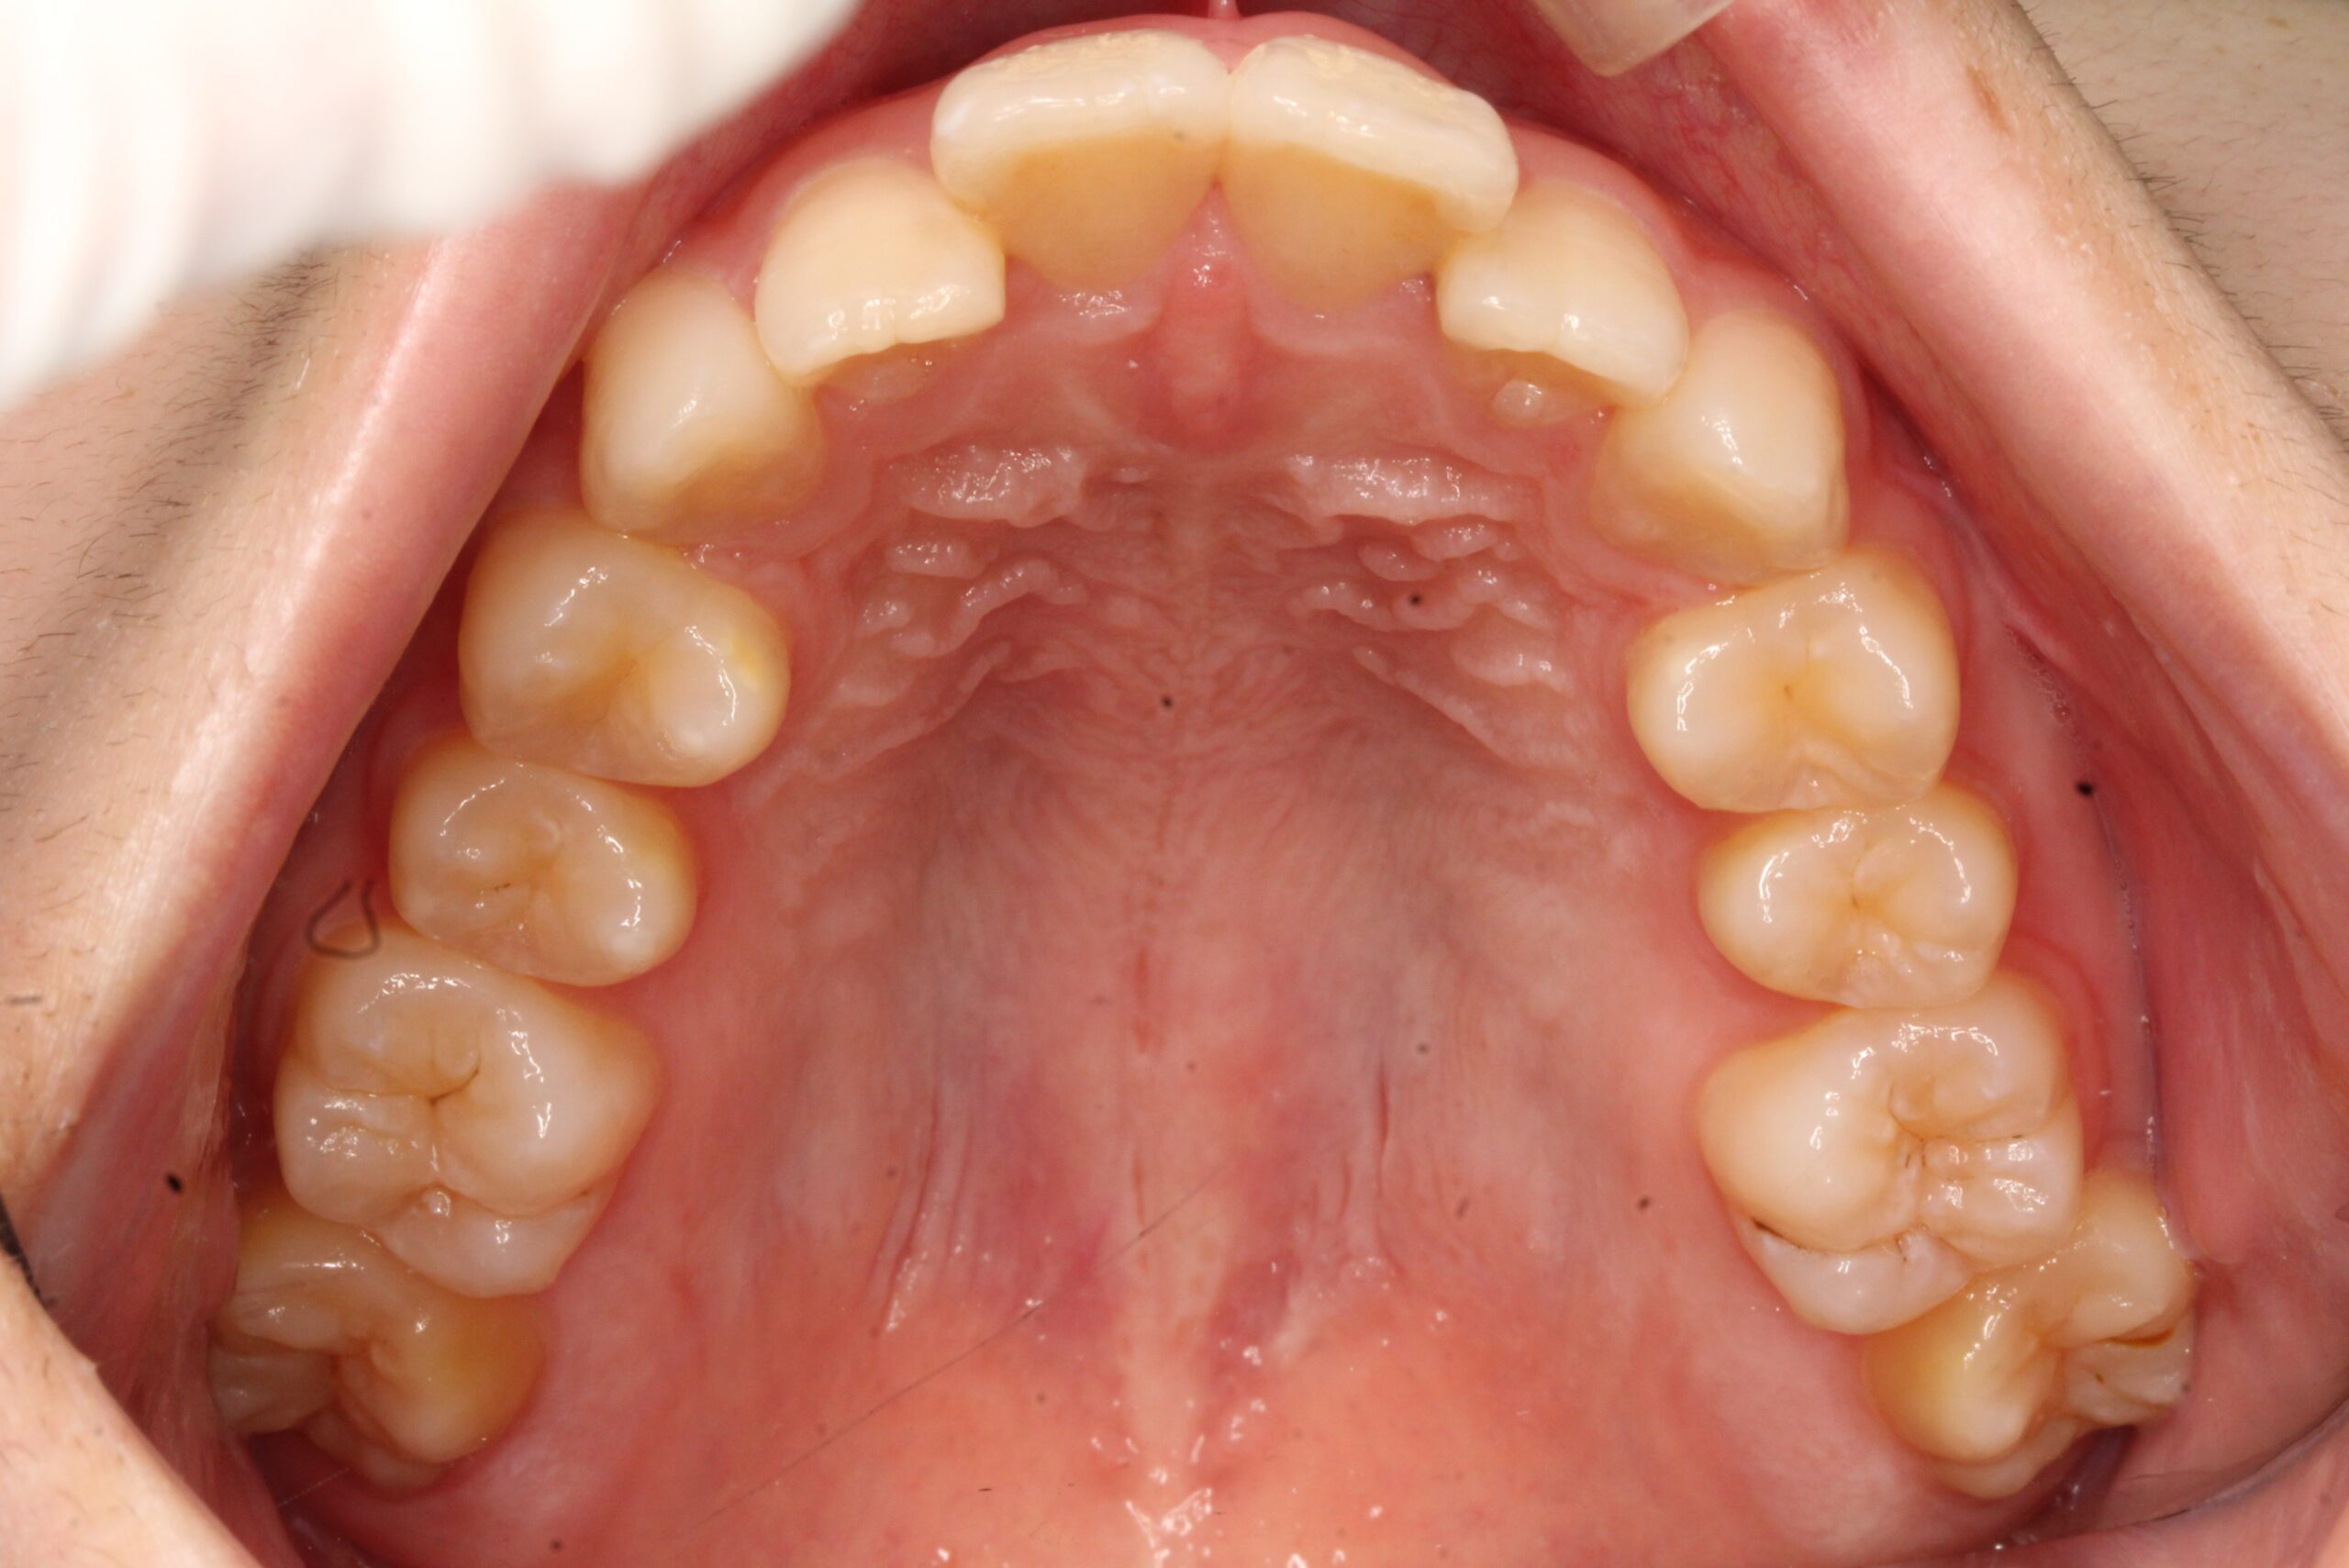

矯正術前:上顎

矯正術後:上顎